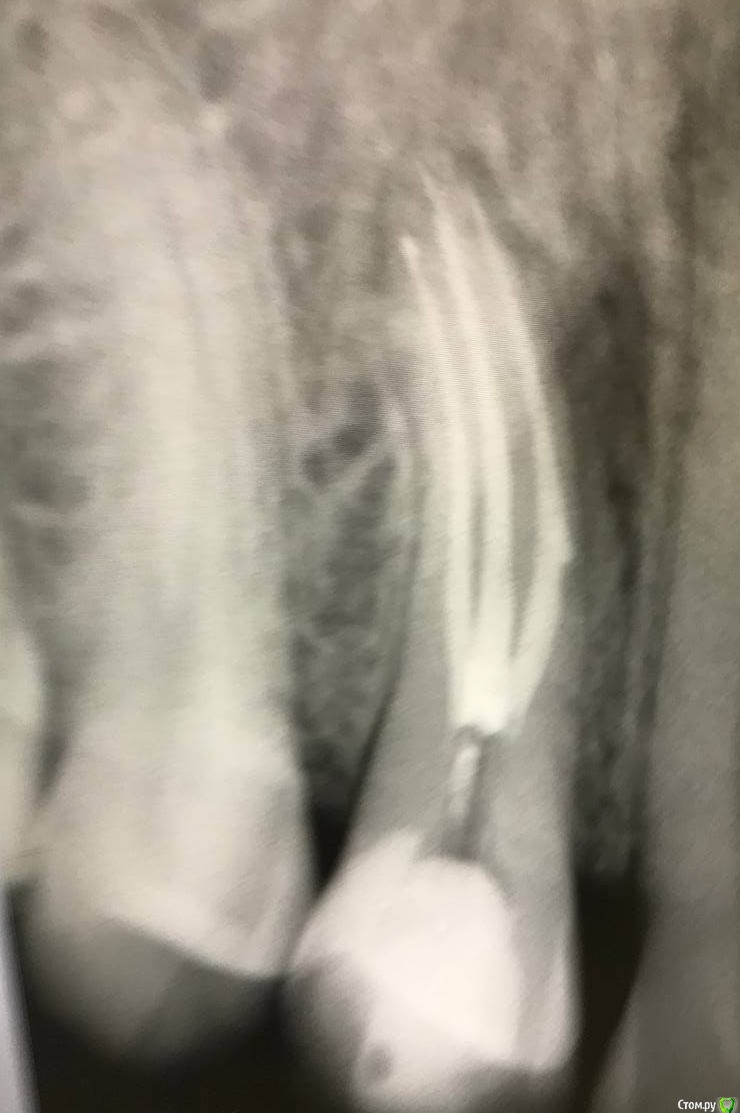

1586Doc Опубликовано 17 января, 2021 Автор Поделиться Опубликовано 17 января, 2021 первые 3 фото, ретрит 14 зуб4.5 фото 45 зуб. 4 Ссылка на комментарий